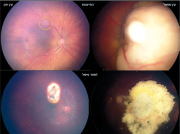

| 07:47, 12 באוגוסט 2023 | רטינובלסטומה3.png (קובץ) |  |

1.5 מגה־בייטים | Motyk | 1 | |

| 07:42, 12 באוגוסט 2023 | רטינובלסטומה 2.png (קובץ) |  |

79 קילו־בייטים | Motyk | 1 | |

| 18:29, 11 באוגוסט 2023 | רטינובלסטומה1.png (קובץ) |  |

83 קילו־בייטים | Motyk | 1 | |